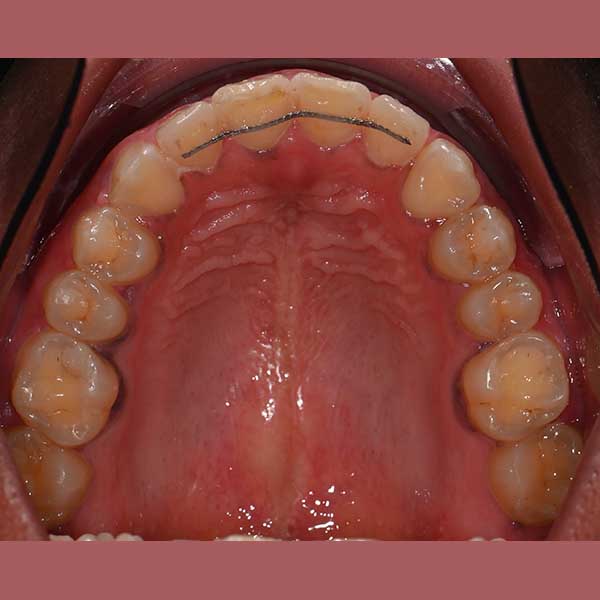

Case: Impacted upper canines – severe overlap – fixed orthodontics

By examining the case and taking X-rays, I observed the upper canines in her mouth, and an embedded lower premolar was observed too on the left side, I started the treat the case, but because of the old age of this lady, the upper canines and the left lower premolar did not erupt on their own after we extracted the temporary canines, and she had to pull them out by braces. As for the lower jaw; The canines were pulled back in place and the embedded premolar was orthodontically pulled.